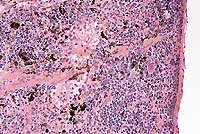

Signalment: 4-month-old, male, 129XC57BL mouse.

History: Injected intraperitoneally with acetaminophen

800mg/kg 48 hours previously.

Conference Note: Conference participants discussed the distinguishing characteristics of the two morphologic expressions of cell death, necrosis and apoptosis.

Necrotic cells show early cytoplasmic swelling and increased eosinophilia, progressing to a more glassy homogeneous appearance than that of normal cells. When cytoplasmic organelles have been enzymatically digested, the cytoplasm becomes vacuolated and appears moth-eaten. Calcification of necrotic cells may occur. Nuclear changes appear in three patterns: karyolysis, a fading of the basophilia of the chromatin reflecting DNAse activity; pyknosis, characterized by nuclear shrinkage and increased basophilia; karyorrhexis, the fragmentation of a pyknotic or partially pyknotic nucleus.

Apoptosis is responsible for cell death in several important physiologic, and some pathologic, processes. These include: 1) programmed destruction of cells during embryogenesis; 2) hormone-dependent physiologic involution; 3) cell depletion in proliferating populations, including tumors; 4) death of lymphocytes after cytokine depletion; and others. The following morphologic features characterize cells undergoing apoptosis:

Apoptotic bodies are rapidly phagocytized and degraded by adjacent healthy cells. In contrast to necrosis, apoptosis does not elicit inflammation. Also, apoptosis usually involves single cells or small clusters of cells. These factors lead to difficulty in detecting apoptosis histologically.

There is considerable interest in the toxicity of acetaminophen, both because of its extensive clinical use and its usefulness in studying mechanisms of hepatotoxicity. This toxicity is believed to be mediated by a highly reactive arylating metabolite formed by the cytochrome P-450-dependent mixed function oxidase system, which is also present in high concentrations in renal proximal convoluted tubular epithelium. After detoxification pathways are impaired and the metabolite is formed in excessive amounts, it can react and covalently bind to cellular macromolecules, causing cellular injury and ultimately leading to cell death. Ray, et al4, recently showed that both apoptosis and necrosis contribute significantly to acetaminophen hepatotixicity in vivo.